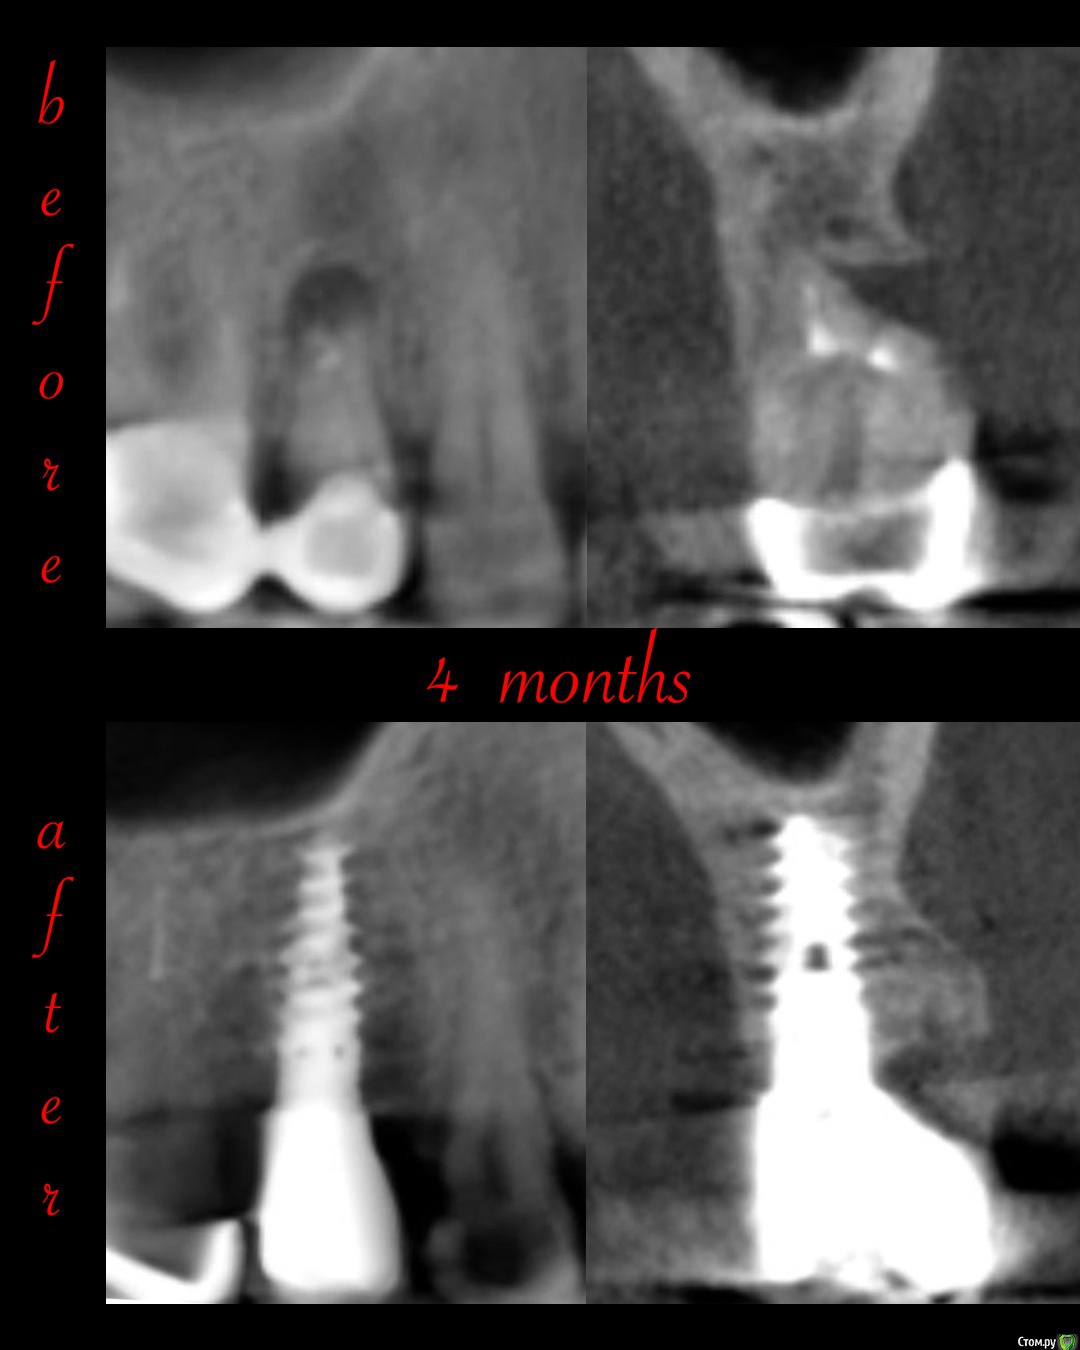

Irouil Опубликовано 29 июля, 2020 Поделиться Опубликовано 29 июля, 2020 Первый полноценный IDR 8 Ссылка на комментарий